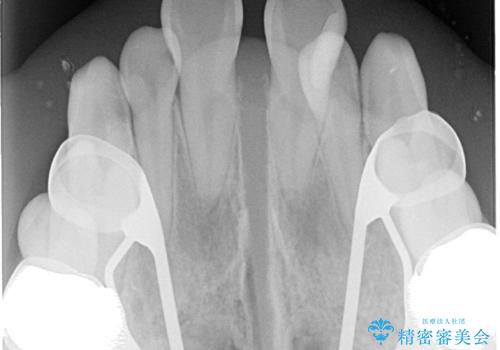

・上下ともに歯がきれいに並びきらず、がたつきが見られました。

・上下の前歯の中心(正中)がずれています。

・特に上顎の幅が狭いため、下顎の歯列も内側に入り込み、歯が並ぶスペースが不足していました。